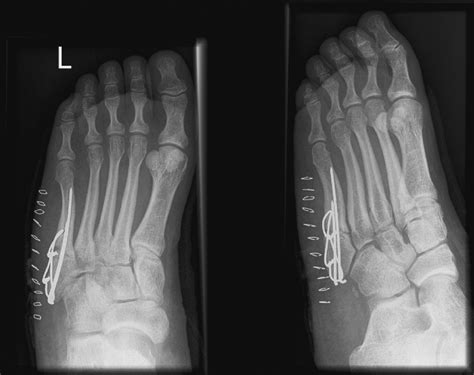

• Surgical Treatment: For more severe or displaced fractures, surgery may be necessary. Surgical options include:

• Open Reduction and Internal Fixation (ORIF): A procedure where the bone is realigned and held in place with screws, plates, or pins.

• Bone Grafting: In cases where the bone is severely damaged, a bone graft may be used to promote healing.